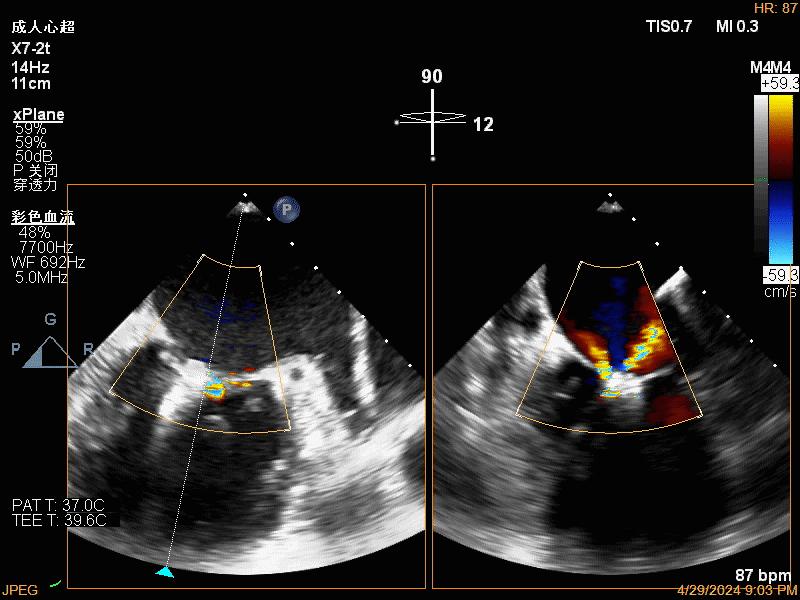

团队在反流最严重的2区精准植入1枚二尖瓣夹,即刻反流下降至微量,血压即刻上升20mmHg,跨瓣压差不升反降,由3mmHg降至2mmHg,改善效果明显,手术仅耗时一个半小时。 这是时隔四年继2020年指导开展区域内首例TAVR(经导管主动脉瓣置换)手术之后,陈茂教授再次带领华西团队,指导开展内自同城区域首例TEER术。陈茂教授对四院心内科心超图像的采集、房间隔穿刺的技巧、手术流程细节的把握、团队的默契配合、术前术后的管理表示称赞,鼓励四院心内科再接再厉造福区域患者。 患者为71岁老年女性,反复出现心累、气促已经超过10年,10多年来心衰的症状逐渐加重,间隔时间越来越短,且近1个月来已经3次因心衰住院,本次住院前已经无法耐受缓慢步行、如厕等日常生活,BNP超过了3000ng/ml。心电图为房颤,心超示左心室明显增大(65mm),重度二尖瓣反流(4+,CarpentierI+IIIb型),射血分数仅为31%。前叶长度:2.27cm且瓣尖增厚,后叶长度:1.14cm且局部钙化,瓣口面积:4.08cm2,反流宽度:1.7cm。患者及家属均拒绝外科开胸手术。 难点: 1.食道超声下该患者房间隔较厚较韧,且粗测高度仅为4.0cm,对穿刺的位置和技巧有较高要求; 2.左心扩大,反流宽度约17mm,放一个夹子可能不能有效解决反流,如放两个夹子需side by side 平行放置,但放置两个夹子有术后狭窄的风险; 3.前后叶对合似有间隙,若选用长宽夹子,会增加瓣叶张力,有瓣叶撕裂的风险,若选用短宽夹子,其捕获瓣叶的难度将增加; 4.患者心功能极差,手术需稳、准、快,不能耐受任何并发症风险。 影像资料 房间隔穿刺